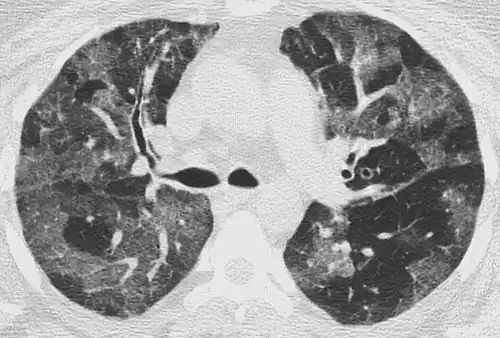

CT image showing patchy areas of ground-glass opacities representing pulmonary edema.